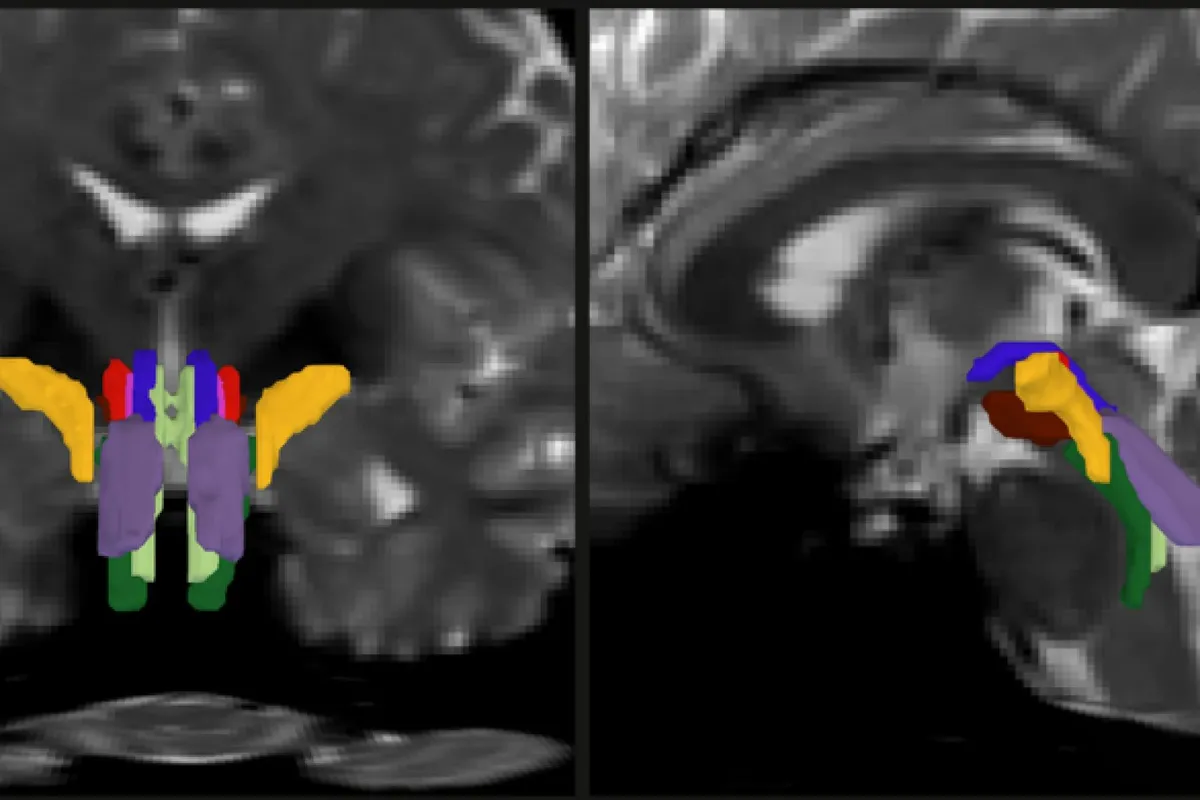

Researchers at MIT, Harvard, and Massachusetts General Hospital have built an AI tool that can automatically map eight distinct fiber bundles in the brainstem with precision that wasn't possible before. Called the BrainStem Bundle Tool (BSBT), it works by combining diffusion MRI scans with a neural network trained to recognize patterns humans would miss. The team published their findings in the Proceedings of the National Academy of Sciences and made the software freely available.

The researchers validated BSBT by training it on 30 brain scans from a public database, then testing it against actual dissections of post-mortem brains — essentially checking their AI against the gold standard of direct observation. It held up. When they scanned 40 volunteers twice, the tool identified the same eight bundles consistently both times.